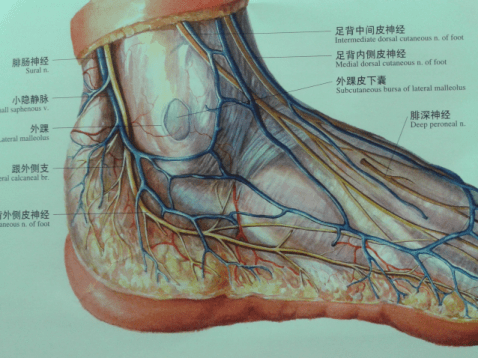

高清图解踝关节韧带解剖

踝关节不稳定4踝伸肌下支持带解剖

值得收藏踝关节解剖分析高清图文详解

踝关节损伤的病因如何处理以及预防措施(附踝关节解剖

踝关节损伤的病因如何处理以及预防措施(附踝关节解剖